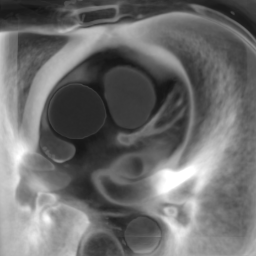

The deformable image registration method is divided into two main stages. For both stages, we used a combination of the CCTA images and segmentation masks. We combined the main cardiac cavities (LV, RV, LA, RA) into a single mask, and combined the aorta (both ascending and descending) and MYO as a second mask (due to the distance between them with low risk of confusion and the advantage of using a small number of masks). In addition, we used two masks corresponding to groups of tissue classified by the density ( and ), after pre-processing the input CCTA images with a median filter with radius 4 to reduce their noise-level and avoid many small objects. The pre-processed intensity images and masks are shown in Fig. 2.

In Fig. 6 we display the mean and standard deviation images after registration, as well as the mean and standard deviation Jacobian determinant images, and the voxel-wise ICE images, for both male and female to enable a visual evaluation of the performance of the registration. See B for additional examples of axial slices, with corresponding visualizations.